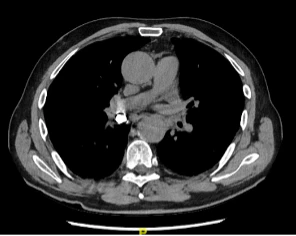

Le CT-scan thoracique, dont on voit ici le scout, met en évidence une structure hyperdense, de densité métallique, au sein de la bronche intermédiaire droite, pouvant correspondre à une couronne dentaire métallique, sans signe d’occlusion complète de la bronche. L’évolution est favorable après récupération de la dent logée dans la bronche intermédiaire droite par bronchoscopie.